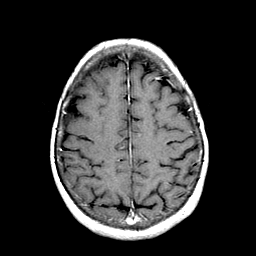

Metastatic Adenocarcinoma of the Colon: T1-weighted MR -- Slice #18

[Home][Help][Clinical] Slice 18